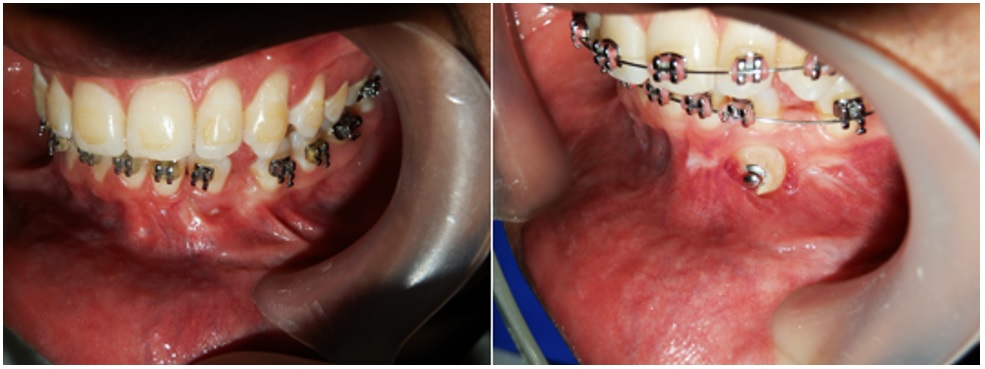

Para iniciar el procedimiento se anestesió la zona con técnica infiltrativa de Seldin con lidocaína al 2 % y epinefrina 1:80.000. Se realizó una incisión en sentido horizontal en la mucosa móvil, en el área de los incisivos laterales inferiores, siguiendo el contorno del fondo del vestíbulo, con mango de bisturí de Bard Parker n.o 3 y hoja de bisturí n.o 15 en dirección perpendicular al campo quirúrgico. Con ayuda de una pinza Adson sin garra se posicionó el tejido vestibularmente para permitir al operador visualizar la zona. Se desbridó mediante un corte agudo hasta llegar al periostio, el cual se eliminó con una espátula 7ª, para exponer hueso. Con ayuda de suturas internas, se ubicó el tejido mucoso en una posición más apical valiéndose del periostio, que estaba por debajo del campo quirúrgico. Se suturó con catgut crómico 4/0. La zona del corte horizontal se dejó sin sutura para promover una cicatrización por segunda intención. Se irrigó con solución salina al 0,9 % y se cubrió la zona con cemento quirúrgico desde el tercio medio de los incisivos inferiores hasta cubrir por completo la herida (figura 1). Al finalizar el procedimiento se prescribió terapia analgésica con nimesulida de 100 mg cada 12 h durante 3 días y antibiótica con amoxicilina de 500 mg cada 8 h durante 7 días. Se dieron además recomendaciones postoperatorias al paciente.

Un hombre de 21 años de edad estuvo en consulta por presentar seudoanodoncia del canino inferior izquierdo (diente 33), mal posición de los incisivos anteriores inferiores, periodonto sano con pérdida de inserción en los incisivos centrales inferiores izquierdo y derecho (dientes 31 y 41, respectivamente) e inserción anómala del frenillo labial inferior. Comentó que se sentía inconforme por la ausencia de su canino inferior izquierdo. En el examen clínico se observó un vestíbulo poco profundo, poca resiliencia, frenillo labial inferior casi imperceptible y recesiones en las zonas anteriores de los dientes 31 y 41. Al sondeo no se encontraron bolsas periodontales o evidencia de encía insertada insuficiente (figura 4). Se clasificó como recesión clase I, según Miller, y se evaluó la necesidad de implementar terapia etiotrópica periodontal por medio de raspado, alisado radicular y profilaxis antes de cualquier consideración quirúrgica. Se decidió llevar a cabo manejo quirúrgico y ortodóntico para corregir la retracción gingival y controlar el riesgo de complicaciones. Se buscaba liberar el diente 33 para luego, con ayuda de un botón ortodóntico y colocación de aparatología fija, retraerlo.